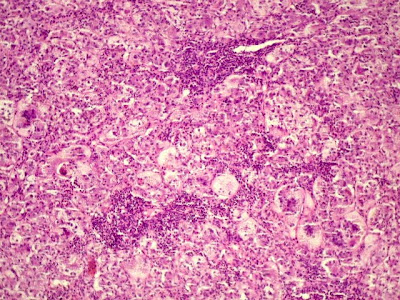

Chamamos de hepatite toda inflamação no fígado. Esta inflamação pode ter diversas causas, como veremos a seguir. Com a inflamação, são destruídas células do fígado (hepatócitos e outros), com diversas conseqüências ao organismo. As hepatites podem ter várias causas. As hepatites virais são todas diferentes em sintomas, gravidade e tratamento. Como as mais comuns aqui no Brasil são as causadas por vírus de nomes semelhantes (A, B e C), muitos pensam que são parecidas. Mas isso foi apenas um modo de facilitar o estudo. A hepatite também pode ser causada por infecções generalizadas que acabam por atacar também o fígado, por substâncias tóxicas como o álcool, por erros do nosso próprio sistema imunológico, por mais de um modo diferente e através de outros mecanismos que ainda não conhecemos. Na hepatite aguda, os sintomas podem variar bastante. Dependendo da causa, eles podem não aparecer. Na maioria das vezes, a hepatite aguda surge com um quadro parecido a de uma gripe, com mal estar, fraqueza, febre, dores e náuseas. Quadros mais intensos podem vir com icterícia, que é um amarelamento da pele e dos olhos causado pelo acúmulo de bile no sangue. Além dos sintomas habituais, surgem alterações de comportamento, sonolência e confusão, sinais de que o fígado não está conseguindo eliminar toxinas do organismo (encefalopatia hepática). Na hepatite crônica, ocorre uma destruição lenta das células do fígado, que aos poucos vão se regenerando ou formando cicatrizes. Nessa fase, praticamente não há sintomas. Por esse motivo, muitas pessoas não descobrem a doença até que seja tarde demais. O que acontece é que a destruição das células do fígado pode chegar a um ponto em que a regeneração não é mais possível e o fígado pode não ser mais capaz de funcionar normalmente. Isso, junto com a formação de cicatrizes no fígado, é o que chamamos de cirrose

NECROSE

Necrose é o estado de morte de um tecido ou parte dele em um organismo vivo. A necrose é sempre um processo patológico e desordenado de morte celular (diferente da apoptose) causado por fatores que levam à lesão celular irreversível e conseqüente morte celular. Alguns exemplos destes fatores são hipóxia/isquemia, agentes químicos tóxicos ou agentes biológicos que causem dano direto ou desencadeiem resposta imunológica danosa, como fungos, bactérias e vírus. A necrose pode ser diferenciada em vários tipos, e cada um está associado a determinado tipo de agente lesivo e determinadas características teciduais após a necrose.